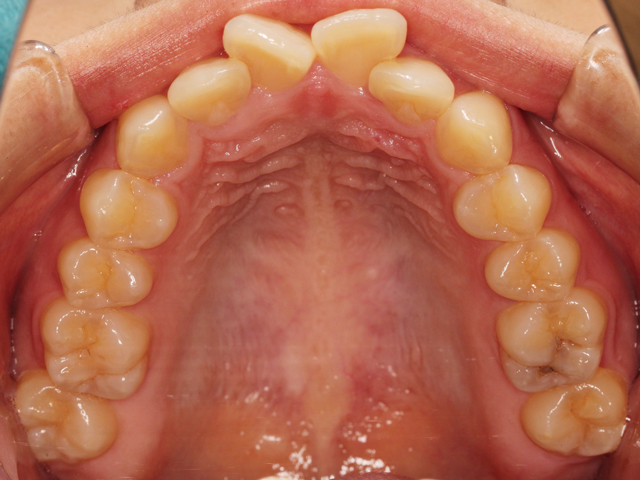

上顎の画像です。前歯のスペースが不足しています。

中切歯が押し出されているように見える状態です。また右上の中切歯は専門用語で「捻転(ねんてん)」と呼ばれる、歯が捻じれている状態です。

正中の中心に向かって捻じれている「近心捻転(きんしんねんてん)」と呼ばれる状態です。